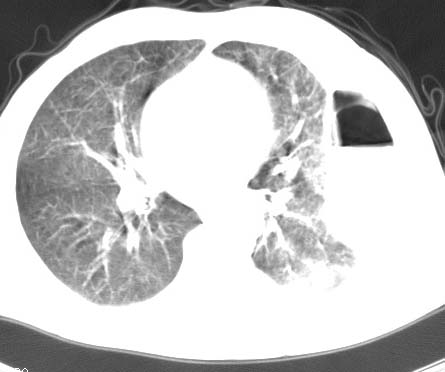

标题: CT10145:男性,30岁,活动后气促2月余.隔疝伴胸腔积液.右上肺结 [打印本页]

男性 病人 30岁,活动后气促2月余.隔疝伴胸腔积液.右上肺结核!

双肺上结核;膈肌裂孔疝。

左侧胸腔积液,并胸腔内见多个含液 气组织,并相互重叠。影像特征很特殊,应该是“膈疝”。支持!

左侧膈疝,及左侧胸水,双上肺结核。

支持!左侧膈疝,左侧胸水,双上肺结核。